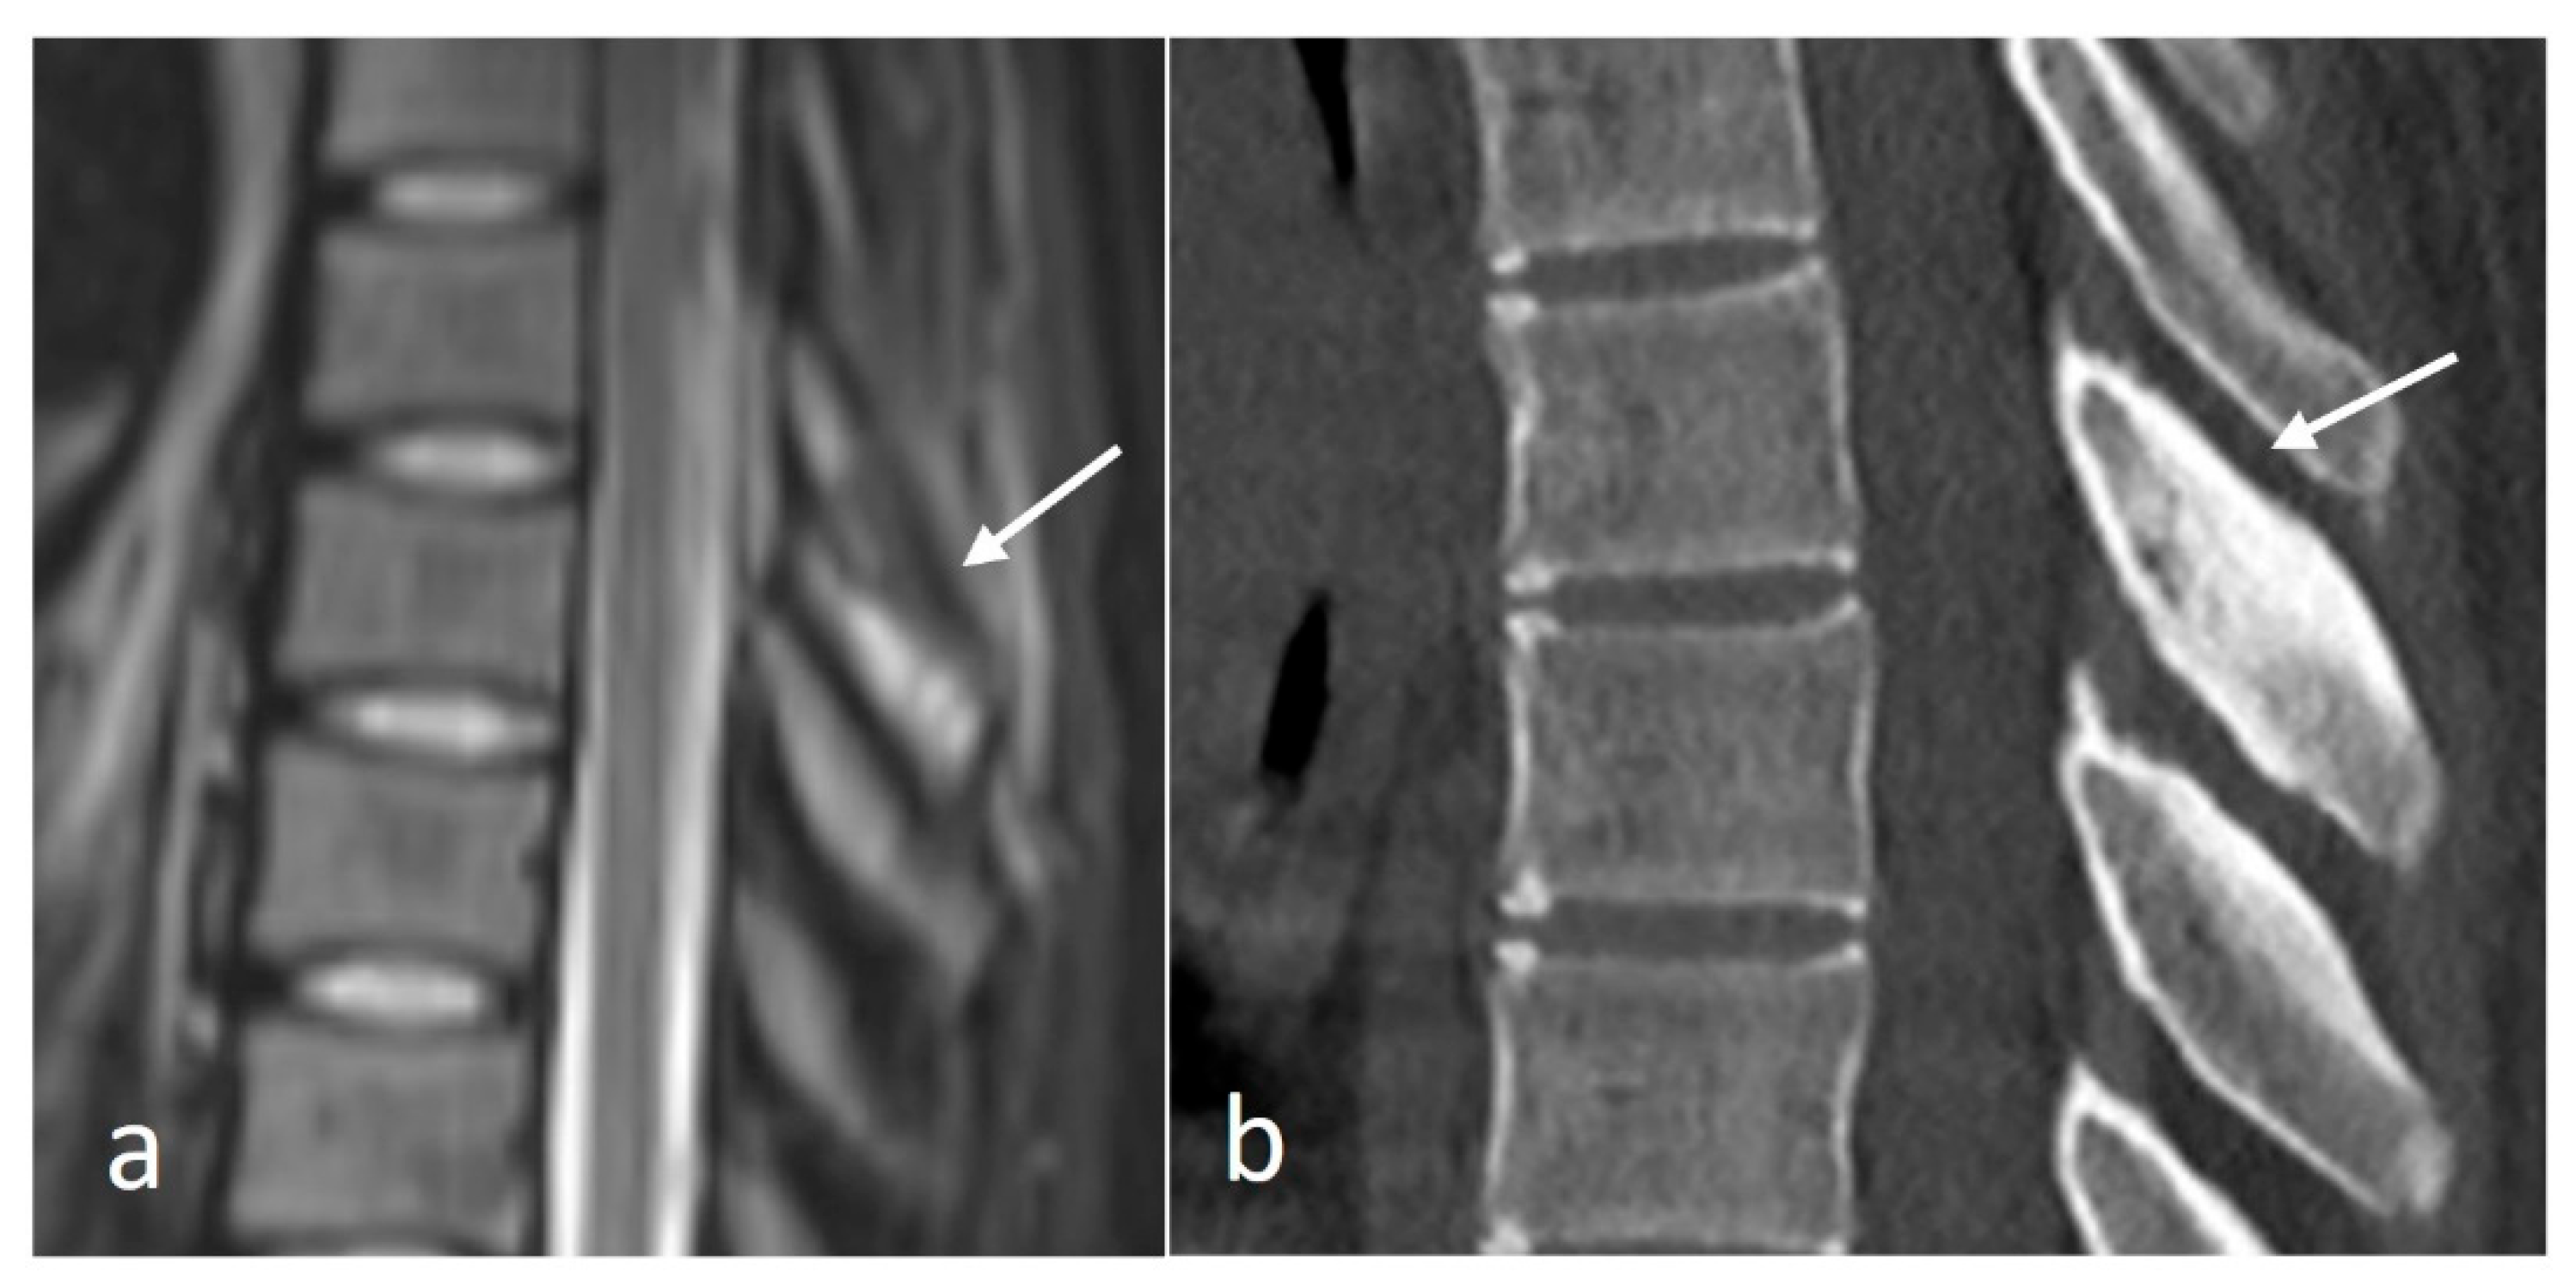

Osteoid osteomas (OOs) account for 10–14% of primary vertebral tumours. The majority are seen in the lumbar spine, followed by the cervical and thoracic spine. Given their predilection for the posterior elements, involvement of the spinous process is not uncommon [15,16]. MRI is sensitive and may show marrow oedema; however, the oedema can obscure the nidus, which can be a potential pitfall. On MRI, the nidus when seen is of low to intermediate T1 signal, ofvariable T2 signal with areas of signal void due to mineralisation (Figure 2a). The nidus may also show variable enhancement on post-contrast imaging [15,16]. Lesions may be occult on a radiograph. The presence of sclerotic reactive bone surrounding a lucent nidus is a typical feature on CT, although the latter may not always be present (Figure 2b). A central sclerotic dot may also be present. The nidus is typically <1.5 to 2 cm in diameter.

Figure 2.

Sagittal STIR (a) and CT (b) images demonstrating a thoracic spinous process osteoid osteoma (white arrows). Note the presence of reactive marrow oedema on the STIR sequence. The sclerotic reactive bone is well delineated on CT, although the lucent nidus may not always be present as in this case.